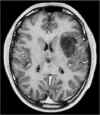

RM preoperatoria

RM

postoperatoria